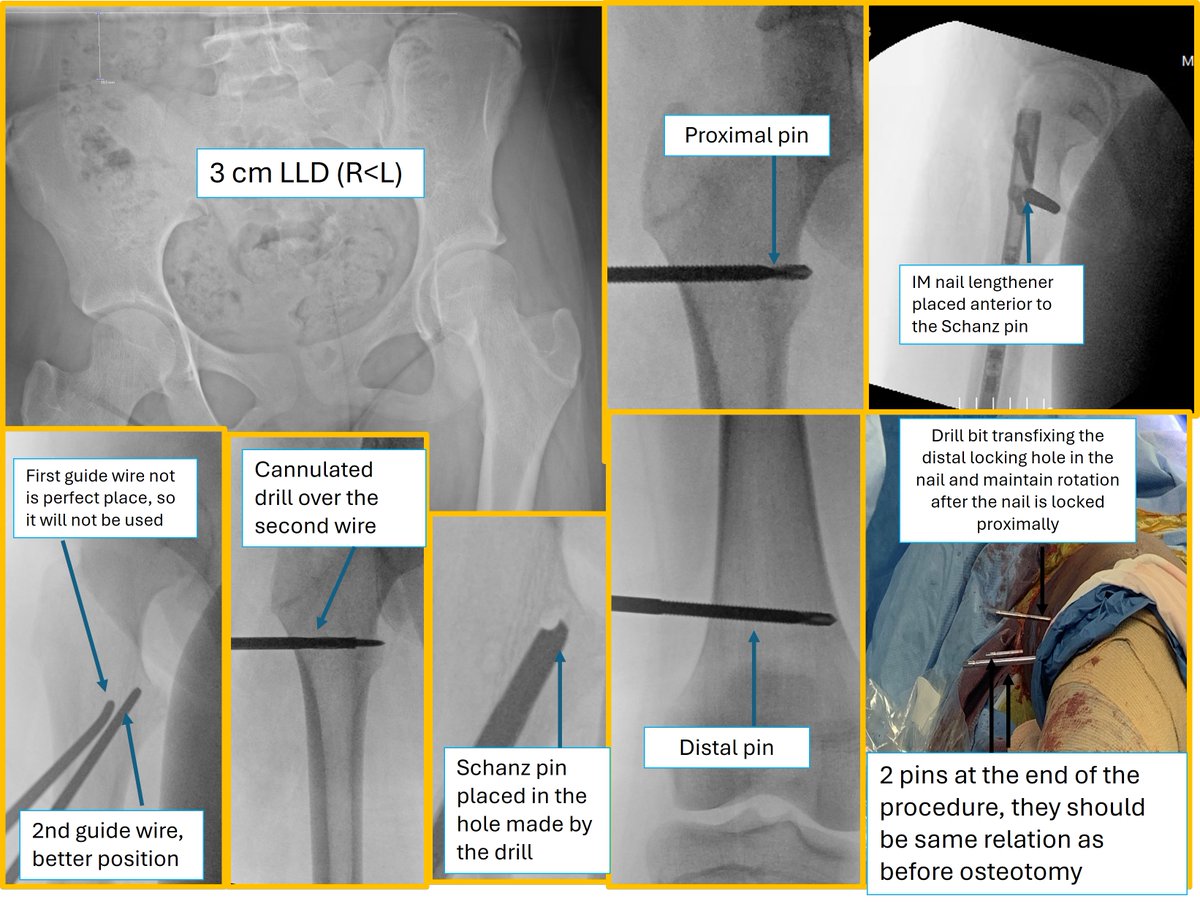

تشرفت بالمشاركة في مؤتمر Egypt Intensive Advanced Professional Limb Reconstruction (EAPLR) الذي أُقيم في الأقصر 2-3 April

استعرض المؤتمر تاريخ وتطورات جراحات تطويل وإعادة بناء الأطراف.

كانت تجربة قيّمة للتعلم وتبادل الخبرات وبناء علاقات مهنية مع زملاء من مختلف أنحاء العالم. كما تشرفت بلقاء عدد من رواد هذا المجال، ومنهم البروفيسور

Maurizio Catagni